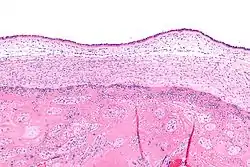

| این اسلاید نشان دهنده کوریوآمنیونیت است. خوشه های آبی رنگ گلبول های سفید و فاکتورهای التهاب می باشند. | |